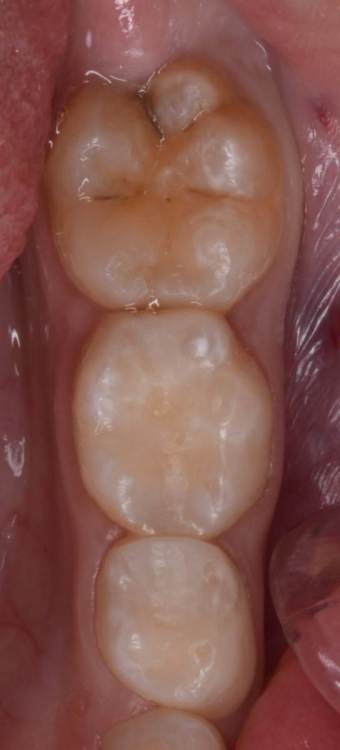

CRAZYDUCK Опубликовано 29 июня, 2022 Автор Поделиться Опубликовано 29 июня, 2022 Герметизация тоже в изоляции . по случаю - герметизация 3.6 лечение кариеса 74 ,75 . 3 1 Ссылка на комментарий